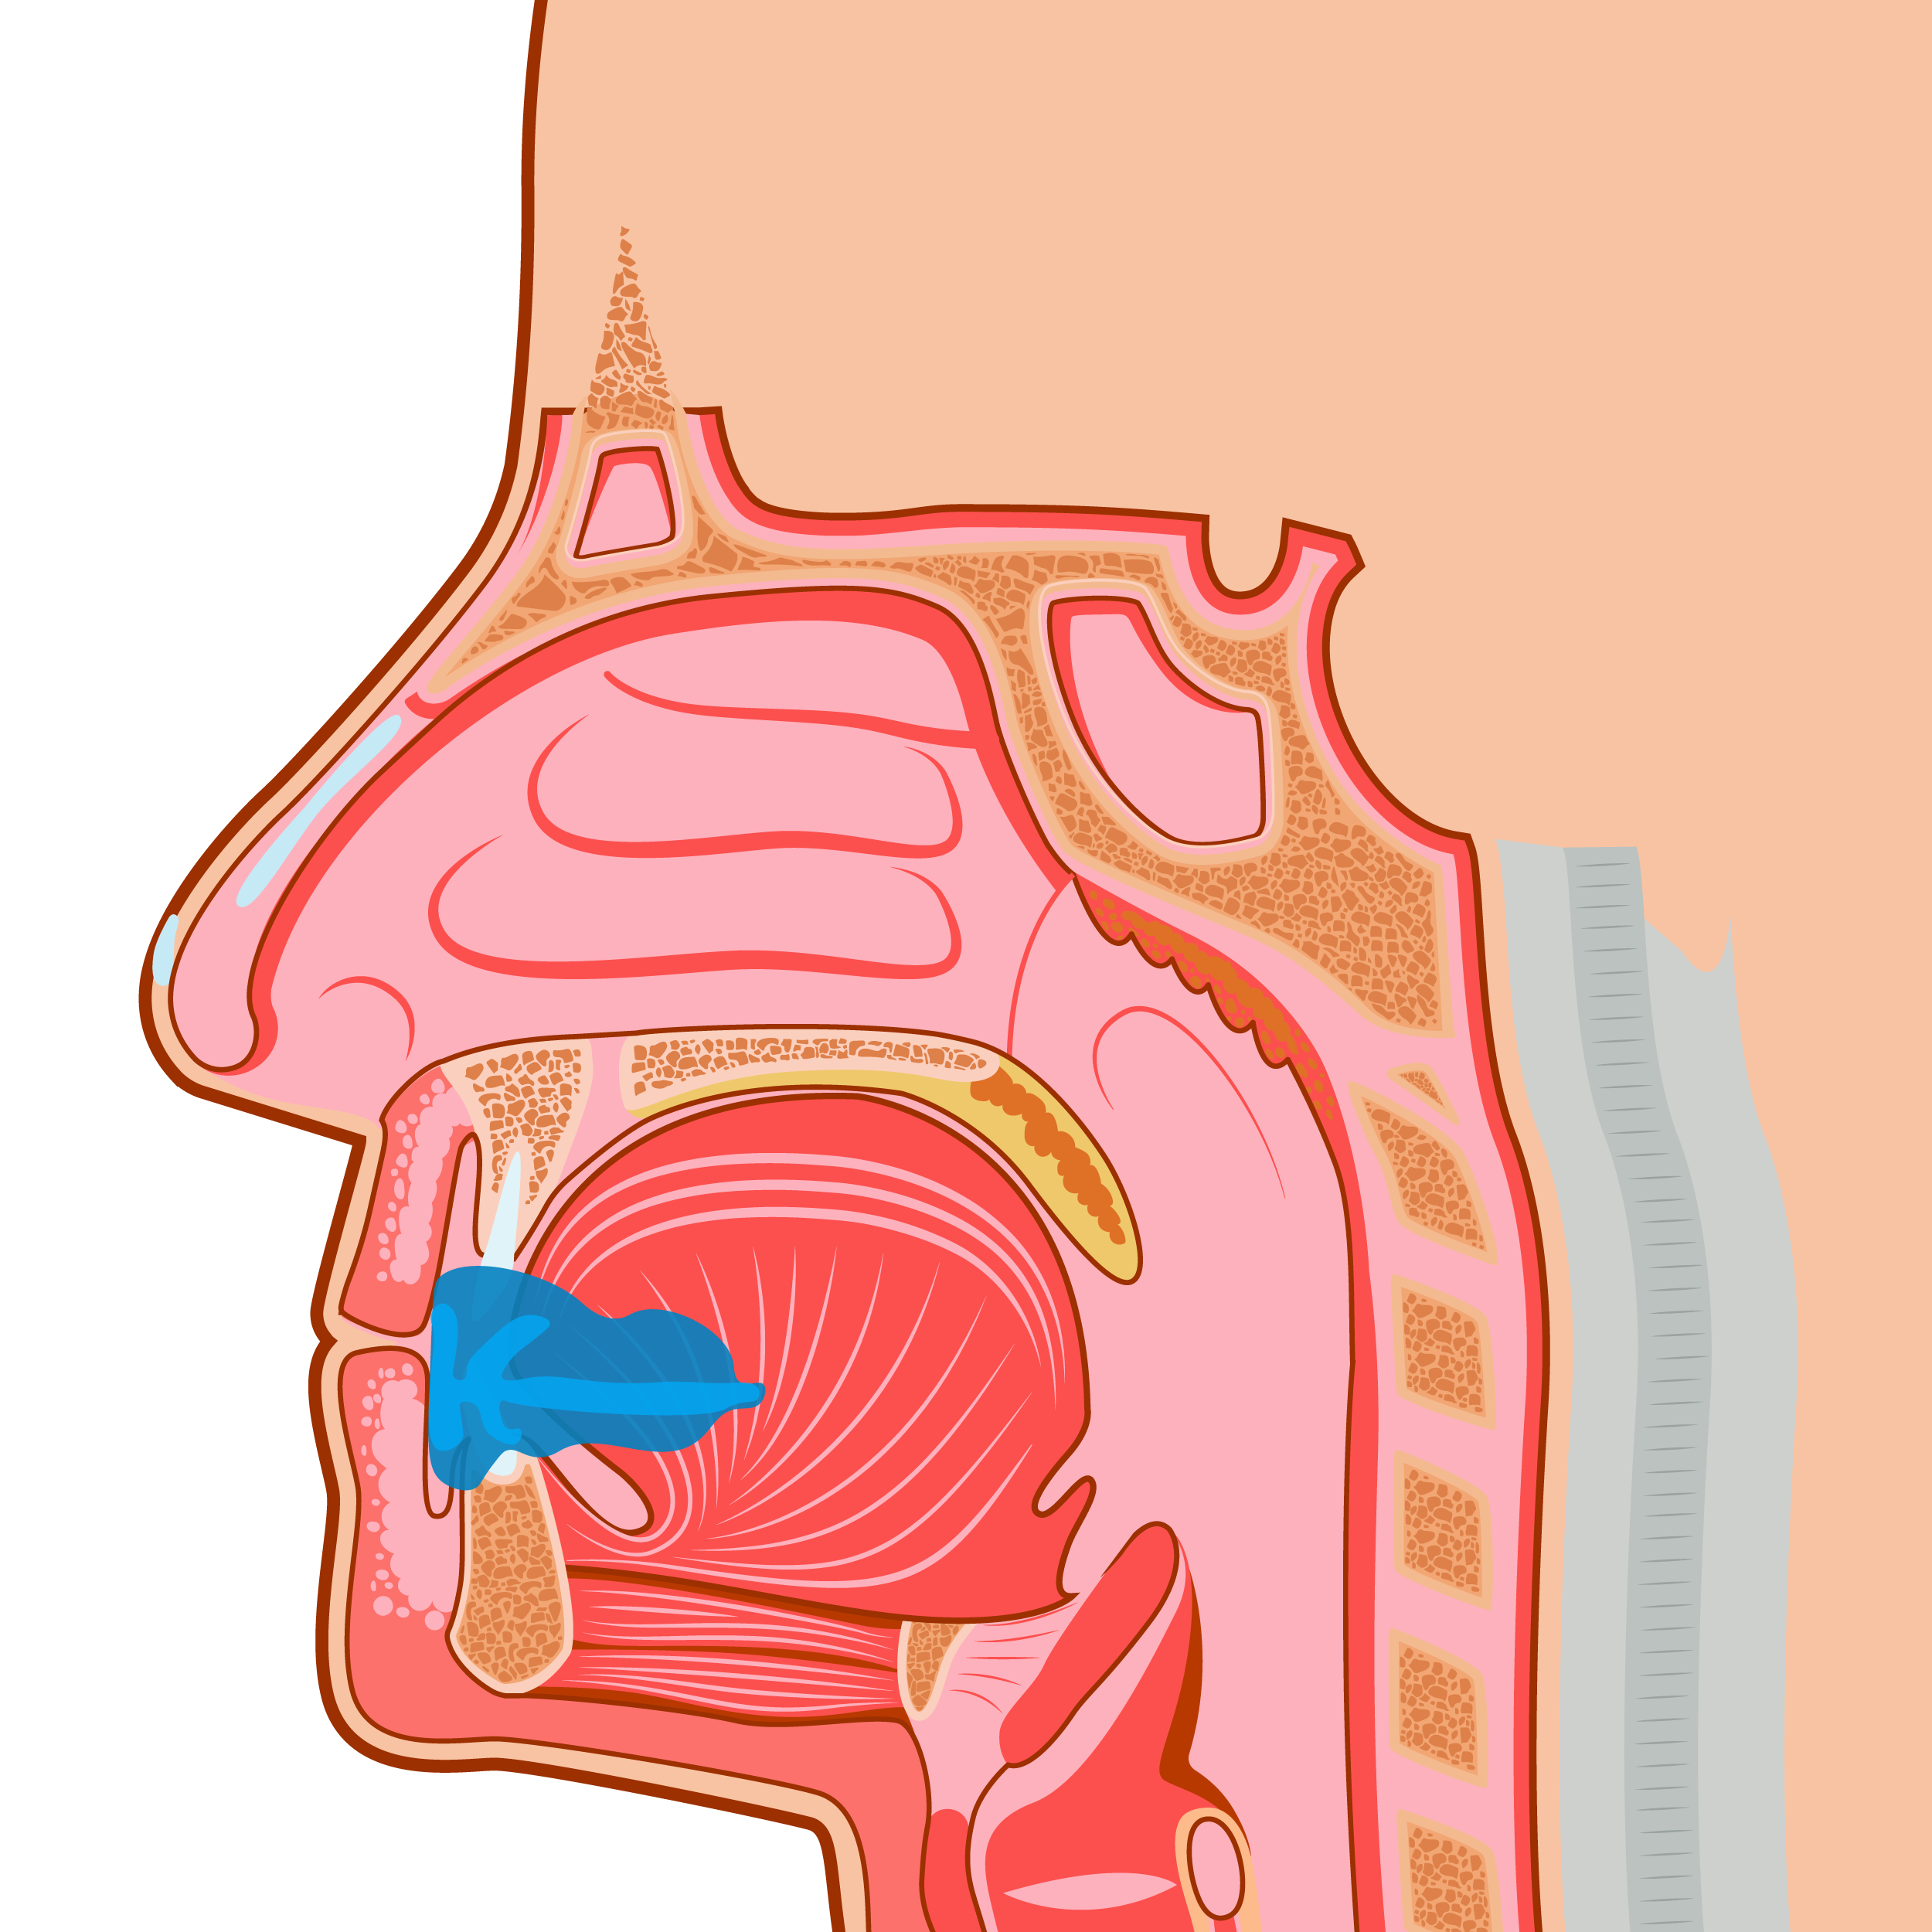

Ronquido

Apnea del sueño

Dolor en la ATM

Malformación orofacial

La odontología Miofuncional es el tratamiento revolucionario que te ofrecerá de una vez por todas.

Myobrace® for Teens es un sistema de Odontología Miofuncional con el objetivo principal de corregir la respiración bucal y los hábitos miofuncionales incorrectos que causan maloclusión, y guía los dientes permanentes para que erupcionen en su alineación natural.

Para el paciente adulto, todo el crecimiento ya se ha producido y los dientes están en su posición más estable. La respiración bucal y los hábitos incorrectos de deglución se han establecido durante muchos años y necesitan ejercicios miofuncionales para ser corregidos.